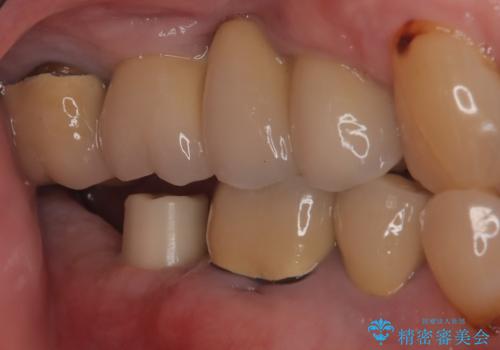

【インプラント】 他院で入れた被せ物が取れた

- 「他院で治療した被せ物が外れた」を主訴に来院された患者様です。診査診断を行い歯の保存が困難だったため抜歯後、インプラントで治療しました。

インプラントを入れるためには十分な骨の高さと幅が必要です。術前に検査を行い必要であれば別途、骨や角化歯肉を増やす治療も行う事があります。

インプラントの土台と被せ物は適合が良い物を制作するため、シリコン印象材を使用し型を取っています。